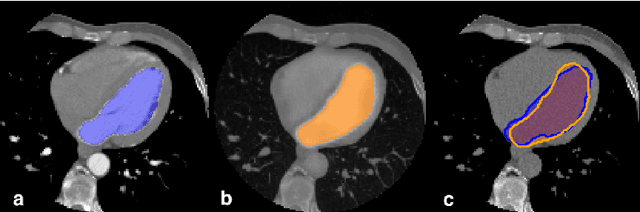

Abstract:In Europe the 20% of the CT scans cover the thoracic region. The acquired images contain information about the cardiovascular system that often remains latent due to the lack of contrast in the cardiac area. On the other hand, the contrast enhanced computed tomography (CECT) represents an imaging technique that allows to easily assess the cardiac chambers volumes and the contrast dynamics. With this work we aim to face the problem of extraction and presentation of these latent information, using a deep learning approach with convolutional neural networks. Starting from the extraction of relevant features from the image without contrast medium, we try to re-map them on features typical of CECT, to synthesize an image characterized by an attenuation in the cardiac chambers as if a virtually iodine contrast medium was injected. The purposes are to guarantee an estimation of the left cardiac chambers volume and to perform an evaluation of the contrast dynamics. Our approach is based on a deconvolutional network trained on a set of 120 patients who underwent both CT acquisitions in the same contrastographic arterial phase and the same cardiac phase. To ensure a reliable predicted CECT image, in terms of values and morphology, a custom loss function is defined by combining an error function to find a pixel-wise correspondence, which takes into account the similarity in term of Hounsfield units between the input and output images and by a cross-entropy computed on the binarized versions of the synthesized and of the real CECT image. The proposed method is finally tested on 20 subjects.